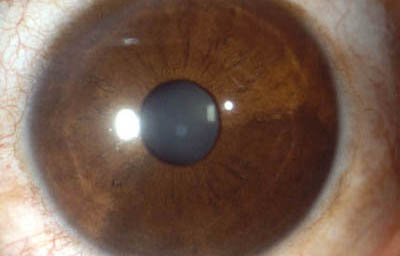

Colobomas típicos con diferentes grados de defecto en el desarrollo

Colobomas Atípicos.

Archivo Fotográfico Dr. Francisco Barraquer

Archivo Fotográfico Dr. Francisco Barraquer